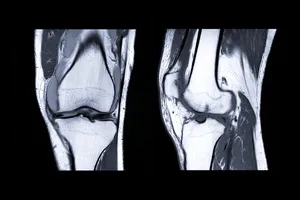

무릎 인공관절수술은 최후의 치료 방법이라는 점을 기억해야 합니다. 수술 전에 충분한 검사와 전문의의 판단을 통해 다른 치료법이 없는지 확인하는 것이 중요합니다.

보통의 진통제나 물리치료로는 통증이 개선되지 않고, 걷기, 계단 오르기, 일어서기 등의 일상적인 활동이 어려워지는 경우 고려할 수 있습니다.

또한, 무릎 관절이 심하게 변형되어 다리가 O 또는 X 형태가 되는 경우, 뼈와 뼈가 서로 마찰하는 모습이 보이는 경우도 고려할 수 있습니다.